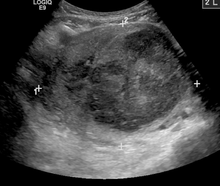

While palpation used in a pelvic examination can typically identify the presence of larger fibroids, gynecologic ultrasonography (ultrasound) has evolved as the standard tool to evaluate the uterus for fibroids. Sonography will depict the fibroids as focal masses with a heterogeneous texture, which usually cause shadowing of the ultrasound beam. The location can be determined and dimensions of the lesion measured. Also magnetic resonance imaging (MRI) can be used to define the depiction of the size and location of the fibroids within the uterus.

A very large (9 cm) fibroid of the uterus which is causing pelvic congestion syndrome as seen on ultrasound